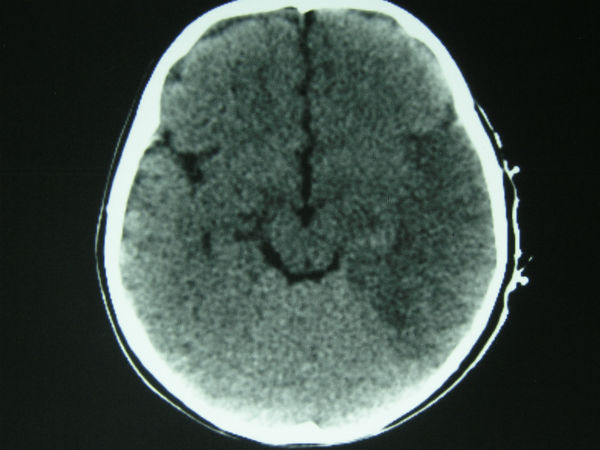

மூளை வீக்க நோய் பாதிப்பு குறித்து கண்டறியும் கருவிகள் கூட அங்குள்ள மருத்துவமனைகளில் இல்லாததால் பெரும்பாலானோர் இறக்க நேரிட்டுள்ளது.